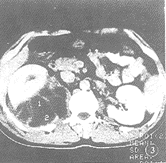

圖1圖1 左腎未成熟膿腫。增強掃描左腎中上極後方類圓形低密度灶,穿破腎包膜,擴展至腎後旁間隙,在此間隙內的病灶液化壞死明顯

圖21例孤立性腎周圍膿腫,平掃顯示右腎向前外方移位,其內後方見大片液性低密度區,間以多數等密度粗大間隔,病變擴展至腎後旁間隙並累及背側肌群。增強掃描示膿腫間隔有中度增強,右腎功能低下(圖3)。

圖3 孤立性腎周圍膿腫。增強掃描右腎向前外後移位,其內後方巨大不規則液性低密度區,間以數個輕中度強化的間隔

圖4急性腎葉性腎炎增強掃描具有典型、特徵性表現,即病變呈楔形或扇形的低密度“葉性損害”,如累及多個腎葉,則可觀察到多個類似的病灶。成熟的腎膿腫呈圓形或橢圓液性低密度灶,有完整的膿腫壁,厚薄均勻,增強掃描壁有明顯強化。未成熟的腎及腎周圍膿腫的診斷有時會遇到困難,增強掃描呈類圓形或不規則狀的“非葉性損害”,有中度不均一強化,如發現腎周圍間隙內有較明顯的液性低密度區及周邊的膿腫壁,腎筋膜和橋隔增厚等徵象,診斷不難成立。如病灶僅有中心部分,且較小的不規則液化壞死區則須注意和腎癌鑑別。腎臟炎性腫塊的診斷困難,平掃及增強表現為腎臟及其相對應腎周圍間隙內的局限性、實質性腫塊,有明顯的占位效應及中度不均一強化,和腎癌表現類似,其診斷應密切結合臨床。